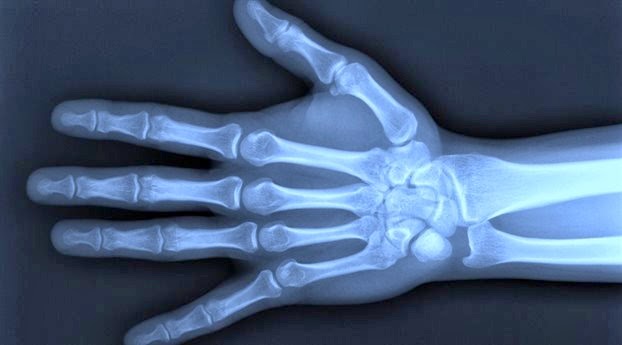

Συμμετρική πολυαρθρίτιδα με κατανομή παρόμοια με αυτή της Ρευματοειδούς Αρθρίτιδας, δηλαδή συμμετρική προσβολή των μικρών κυρίως αρθρώσεων των χεριών και των ποδιών – σήμερα φαίνεται να είναι ο συχνότερος τύπος.

Προσβολή των τελικών (άπω) αρθρώσεων των δακτύλων που συνοδεύεται συνήθως από αλλοιώσεις των νυχιών.

Τα ευρήματα της κλινικής εξέτασης είναι αυτά που συνήθως οδηγούν τον ιατρό στη διενέργεια ορισμένων εργαστηριακών και απεικονιστικών εξετάσεων για να τεθεί τελικά η διάγνωση της ΨΑ. Πώς αντιμετωπίζεται η ψωριασική αρθρίτιδα; H θεραπεία της ψωριασικής αρθρίτιδας έχει ως στόχο την ανακούφιση των ασθενών μέσω του ελέγχου των συμπτωμάτων και της φλεγμονής, την επιβράδυνση της εξέλιξης της νόσου, τη διατήρηση καλής λειτουργικότητας και τη βελτίωση της ποιότητας ζωής των ασθενών.